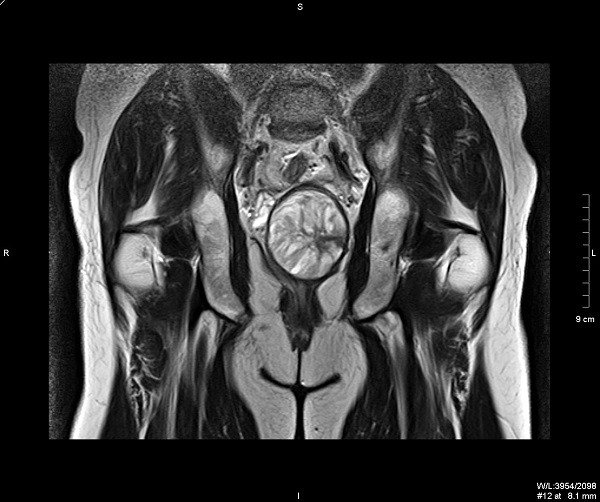

МРТ малого таза у мужчин и женщин покажет состояние органов мочеполовой и выделительной систем, а также кровоснабжающих сосудов брюшной полости. Основными симптомами для назначения диагностики выступает боль в нижней части живота, затруднение мочеиспускания, болезненные менструации, бесплодие, травмы малого таза, врожденные аномалии развития прямой кишки и т. д. У мужчин МРТ таза покажет: У женщин МРТ поможет определить причину нарушения менструального цикла, оценить состояние маточных труб, яичников, влагалища, выявить полипы, кисты, различные воспалительные процессы. Такой безболезненный и эффективный метод диагностики позволит определить множество заболеваний. Врачи назначают МРТ малого таза в случае подозрения на патологический процесс внутренних органов, перед операцией, для уточнения диагноза. Что показывает МРТ малого таза с контрастом? Проведение томографии с контрастным веществом рационально в том случае, если необходимо получить более детальное изображение дл

МРТ малого таза у мужчин и женщин покажет состояние органов мочеполовой и выделительной систем, а также кровоснабжающих сосудов брюшной полости.

Основными симптомами для назначения диагностики выступает боль в нижней части живота, затруднение мочеиспускания, болезненные менструации, бесплодие, травмы малого таза, врожденные аномалии развития прямой кишки и т. д.

У мужчин МРТ таза покажет:

• сосудистые нарушения;

• простатит;

• наличие каких-либо новообразований.

У женщин МРТ поможет определить причину нарушения менструального цикла, оценить состояние маточных труб, яичников, влагалища, выявить полипы, кисты, различные воспалительные процессы.

Такой безболезненный и эффективный метод диагностики позволит определить множество заболеваний. Врачи назначают МРТ малого таза в случае подозрения на патологический процесс внутренних органов, перед операцией, для уточнения диагноза.